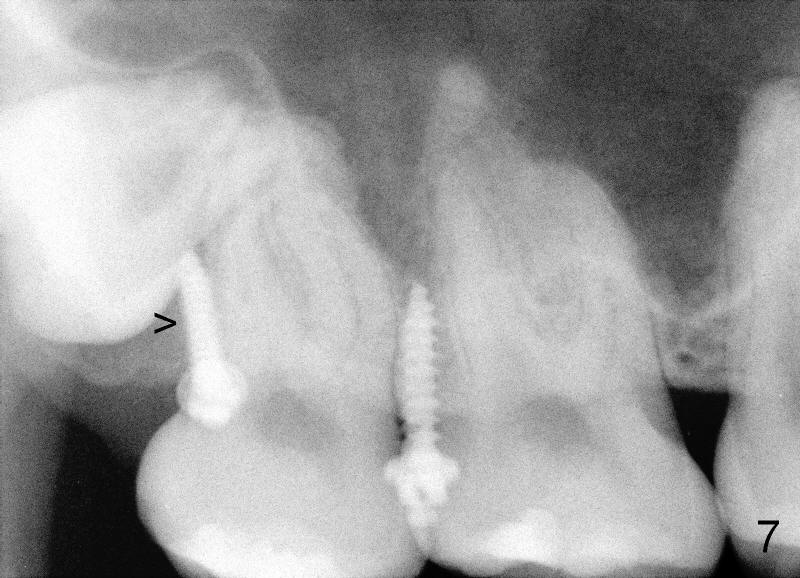

Eight mm of Ancor mini-implant is placed on the mesiobuccal of #2, whereas 6 mm on distopalatal (Fig.3,6 <) without sign of hemorrhage. But a few days later, the patient's father calls, saying that one of mini is out (palatal). The palatal mucoperiosteum is thicker than buccal. Longer mini-implant should have been used (8 or 10 mm). The excuse for short mini in the palate is that there is not much soft tissue (presumably hard tissue) distal to #2. In fact, the patient is dental phobic. Who will faint first dealing with the fearful patient for the same procedure for a second time?

Fortunately, the kid is getting more mature each time. He is pleased to hear that no needle is needed. Another mini company (Tomas, Dentaurums) recommends topical and no incision for mini. Without local anesthesia, the patient may feel pain if a long mini is touching root surface. To get decent anesthesia, Cetacaine (a topical usually used for laser) is applied to the mucosa for prolonged period of time. A 10 mm Ancor mini is loaded in a 16:1 reduction slow-speed handpiece driven by air turbine. The mini penetrates the mucosa without incision or pilot drill. Judged by healed wound, the new mini is placed more mesioapical than the earlier one (Fig.3 *) in hope to catch bone. It appears that the whole hard palate has attached gingiva. The portion near the teeth has thicker gingiva. Mini should be placed in thick gingiva to reduce tissue reaction.

Mini penetration does create soft tissue shaving, which may cause epithelial entrapment and therefore potential mini loosening. At time of placement, it is a minor issue, in comparison to violation of root surface. As the mini goes down, torque builds up. Finally the handpiece halts. Then use a wrench to slowly rotate the mini down while watching for patient's reaction. It appears that the mini eventually has resistance (touching root surface?). The mini does not seat completely (Fig.4 >, as compared to Fig.3 <), but it is solid. When power chain is loaded, it is apparent that the patient feels more pressure upon #2. The patient tolerates the procedure with topical well. It feels like that champagne is needed for celebration. Sweeter is taking and looking at immediately post-op PA (Fig.7 >).